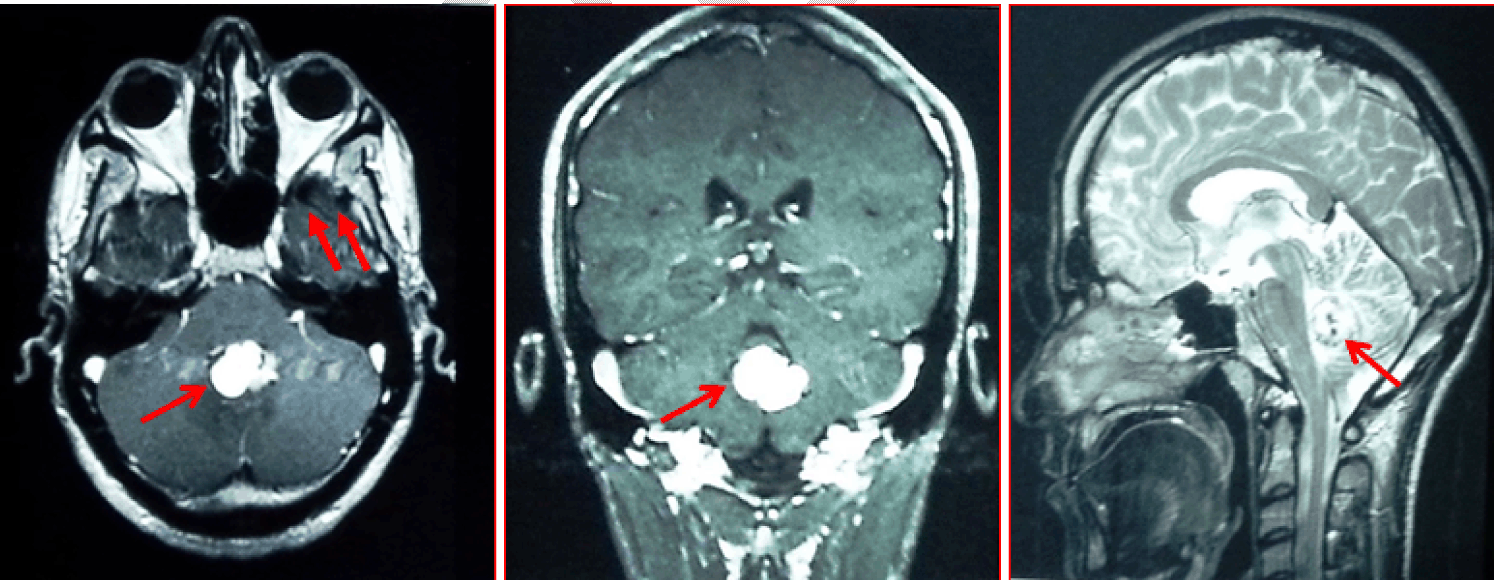

Figure 3: Magnetic resonance imaging scan of the brain showing a vermian hemangioblastoma associated with 2 small right cerebellar hemangioblastomas.

The patient underwent an MRI of the complete neuro-axis including brain and spinal cord showed a vermian hemangioblastoma associated with 2 small right cerebellar hemangioblastomas (Figure 3). The abdominal CT scan revealed 2 small renal masses, less than 2 cm in size; with multiple pancreatic cysts (Figure 4); without liver lesions, or adrenal masses. An ophthalmologic examination demonstrated none of the stigmatisms associated with VHL. Physical examination did not show any café au lait spots.